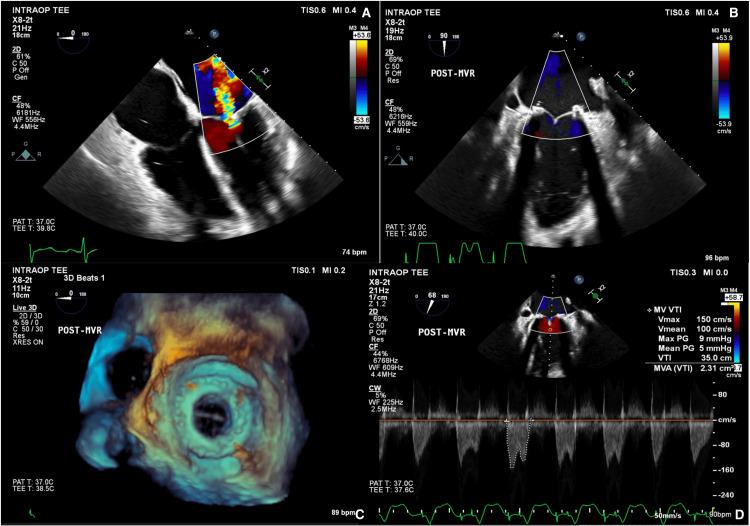

Hypoprothrombinemia is a rare coagulopathy that complicates surgical interventions and is an uncommon manifestation of lupus anticoagulant. Perioperative coagulopathy is a major challenge in cardiac surgery. To our knowledge, the management of cardiac surgery in patients with hypoprothrombinemia has not been described in prior literature. This case report outlines the challenging surgical intervention of mitral valve replacement in a 47-year-old female patient with rheumatic valve disease (RHD) and a rare prothrombin deficiency secondary to lupus anticoagulant. This report details the multidisciplinary perioperative hemostasis management and outcomes.

低凝血酶原血症是一种罕见的凝血病,会使外科手术复杂化,也是狼疮抗凝物的一种不常见表现。围手术期凝血病是心脏手术中的一项重大挑战。据我们所知,先前文献中尚未描述过低凝血酶原血症患者的心脏手术管理。本病例报告概述了一名47岁患有风湿性瓣膜病(RHD)且因狼疮抗凝物继发罕见凝血酶原缺乏的女性患者进行二尖瓣置换的具有挑战性的外科手术。本报告详细介绍了多学科围手术期止血管理及结果。